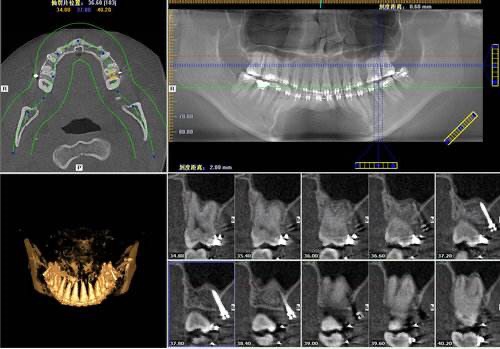

CBCT片

随着生活水平的提高,人们对牙科病,牙齿矫形等越来越重视,口腔曲面断层摄影在临床诊疗中的应用越来越广泛。为满足患者及临床需求,为临床提供更精确的诊断信息,我院购买了KaVo的ORTHOPANTOMOGRAPH OP 3D Pro口腔锥形束计算机断层扫描设备(CBCT),已安装调试投入临床使用。

成像质量高:扫描层薄,无需断层之间重建,金属伪影轻。